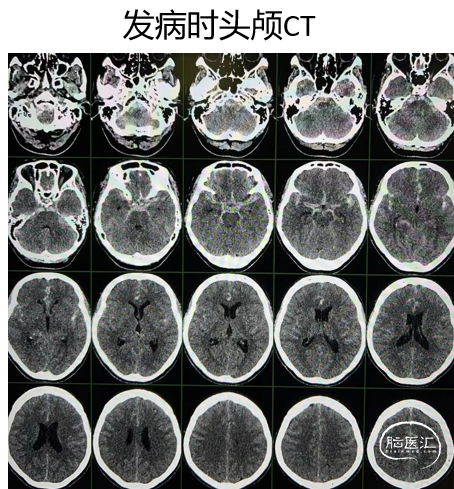

头颅CT

术前

术后第一天

术后第一天复查头颅CT

术后CT

术后CT